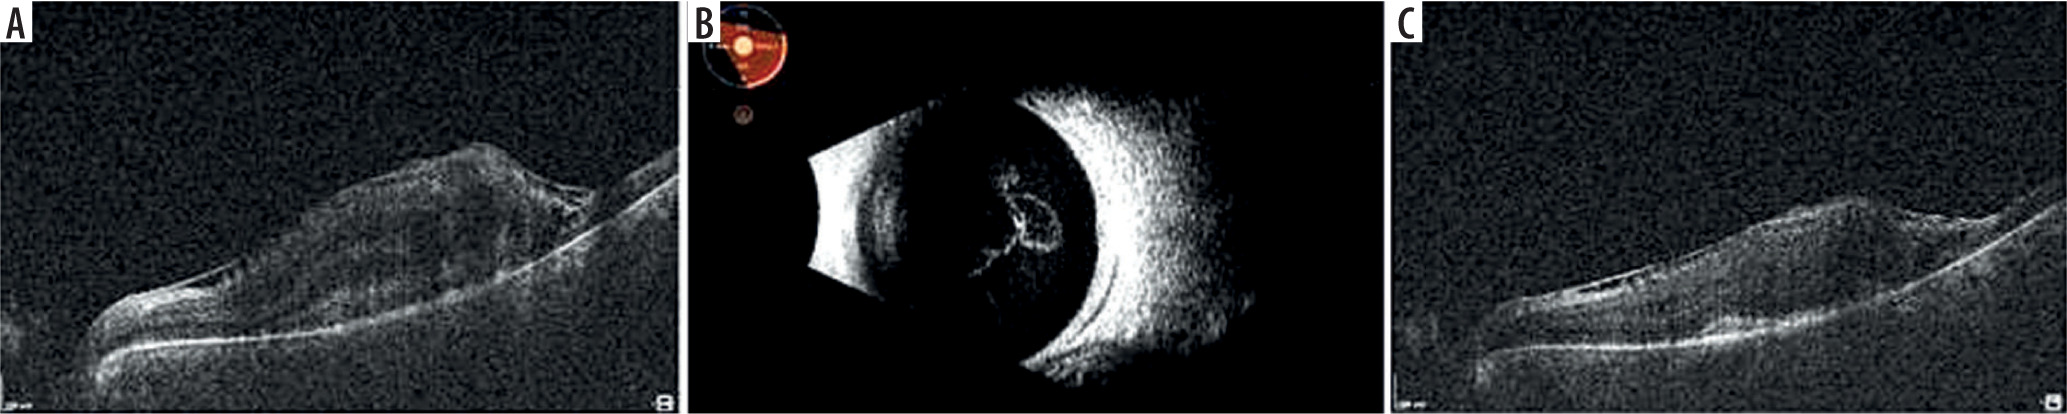

A 54-year-old woman was hospitalized due to necrotic retinitis of her left eye (LE). She noticed floaters and decrease of visual acuity (VA) one month earlier with concomitant general weakness. As she experienced the similar floaters in her right eye (RE) about one year earlier with its spontaneous resolution, she did not initially seek medical attention. Her medical history was notable for peripheral spondyloarthropathy (HLA-B27+) for 10 years. The disease had been controlled by oral MTX 25 mg once weekly for 3 years, methylprednisolone 3 mg daily for 10 years, and nonsteroidal anti-inflammatory drugs (NSAIDs). She also suffered from post-steroidal diabetes and osteoporosis. At admission her VA (Snellen) was 1.0 and 0.4 for RE and LE, respectively. Right eye showed atrophic perifoveal scar (Figure 1A) and LE mild anterior segment inflammation. Fundus eye examination found vitreous inflammatory opacities and large nonhomogeneous inflammatory lesion with signs of diffuse arteritis (Figure 1B). Fluorescein angiography (FA) showed the hypofluorescence area with hyperfluorescent center (Figure 1C). Serology testing was notable for toxoplasma (IgG > 200, positive if > 3.0, and IgM 0,48, negative if < 0.5), cytomegalovirus (CMV; IgG 177, positive if > 6.0, IgM not reactive) and herpes zoster virus (HZV; IgG 448.47, positive if > 110, IgM negative). Syphilis, HIV, and herpes virus type 1 and 2 were negative. Blood count revealed slightly decreased levels of monocytes and lymphocytes. Methotrexate treatment was discontinued due to immunosuppression. Oral trimethoprim/sulfamethoxazole (TS) twice a day and clindamycin 1 mg intravitreally twice with an interval of 5 days were given. Additionally, oral acyclovir 800 mg 5 times per day was prescribed. In the following 10 days of hospitalization, the inflammation decreased and VA increased to 0.5 (Figure 1D). Patient was discharged from the hospital on methylpredniso-lone and TS. At the 3-week follow-up, massive retinal neovascularization was found with persistent retinal inflammation (Figure 2A–C). Two complementary intravitreal injections of clindamycin resulted in rapid improvement. The signs of arteritis almost disappeared, and panretinal photocoagulation was urgently done. Prophylactic doses of TS (1 tablet every 3 days) were prescribed. On follow-up, VA was gradually decreasing to 0.02 due to progressive macular edema and membrane (Figure 3A). At the 8-month follow-up visit spontaneous posterior vitreous detachment (PVD) with concomitant vitreous hemorrhage occurred and VA was hand movements (Figure 3B). Anti-VEGFs (aflibercept twice and faricimab once) were injected in case of macular edema aggravation. At the 18-month follow-up visit VA was 0.1 (Figure 3C).